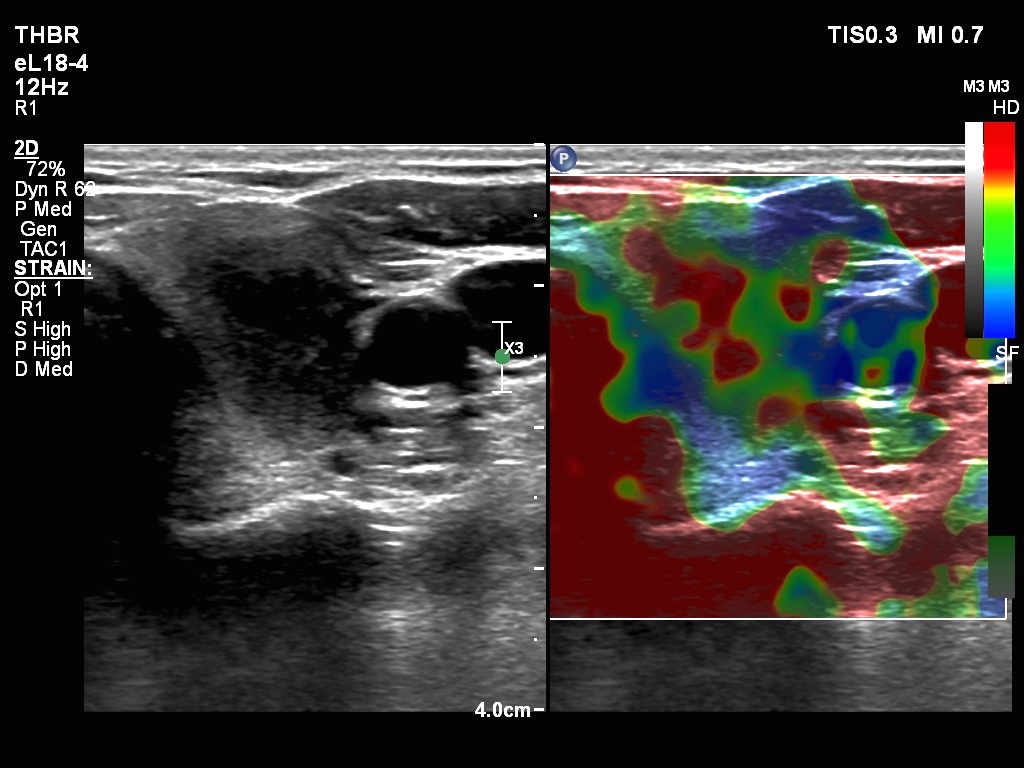

Right lobe, longitudinal scan

Upper part of the left lobe, transverse scan, elastography. The central part of the focus of thyroiditis proved to be rigid.